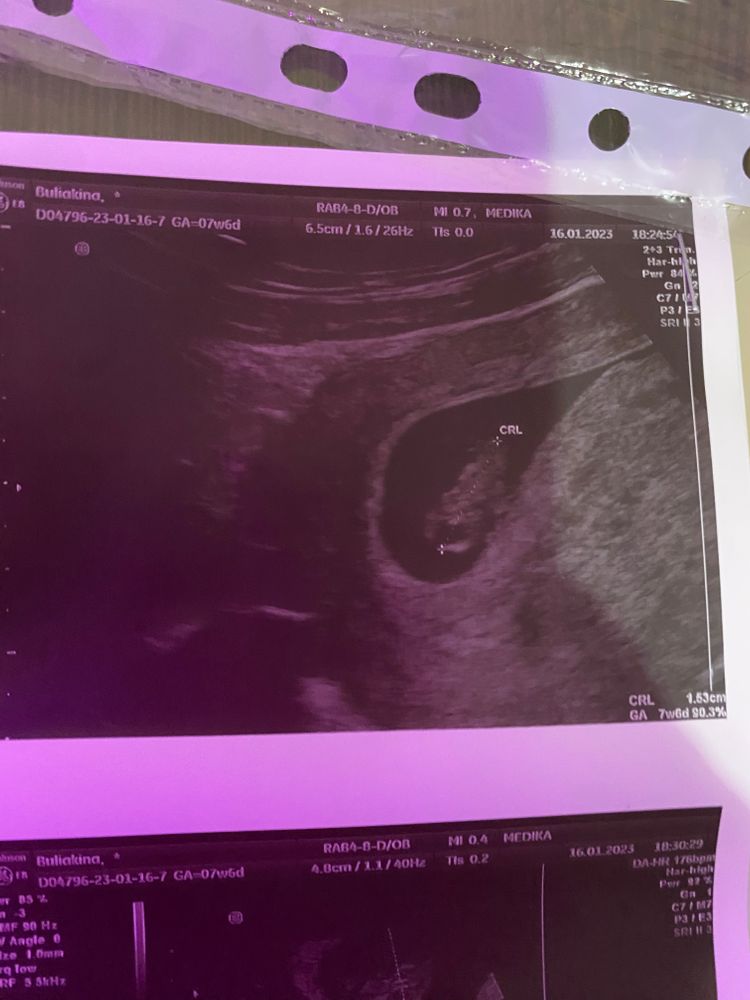

8 неделек 🥰

Katun, нет. Но она и небольшая была 1,6см на 1см

DariaZhar, у меня неделю назад тоже увидели маленькую 8х3, а сейчас подмазывает. Вот думаю может это гематома выходит.

Узи 7 недель Беременность